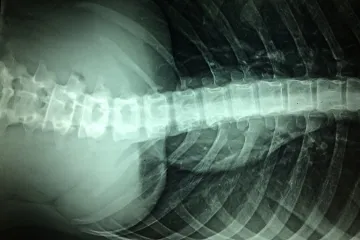

Lékaři z Yaleovy univerzity opravili narušenou míchu pomocí kmenových buněk

Poranění páteře patří mezi ta nejhůře léčitelná. Lékaři nyní informují o úspěchu s léčbou pomocí kmenových buněk. Injekce těchto buněk z kostní dřeně vedly u pacientů k významnému zlepšení motorických funkcí, uvedli vědci z Yaleovy univerzity a Japonska v odborném časopise Journal of Clinical Neurology and Neurosurgery.